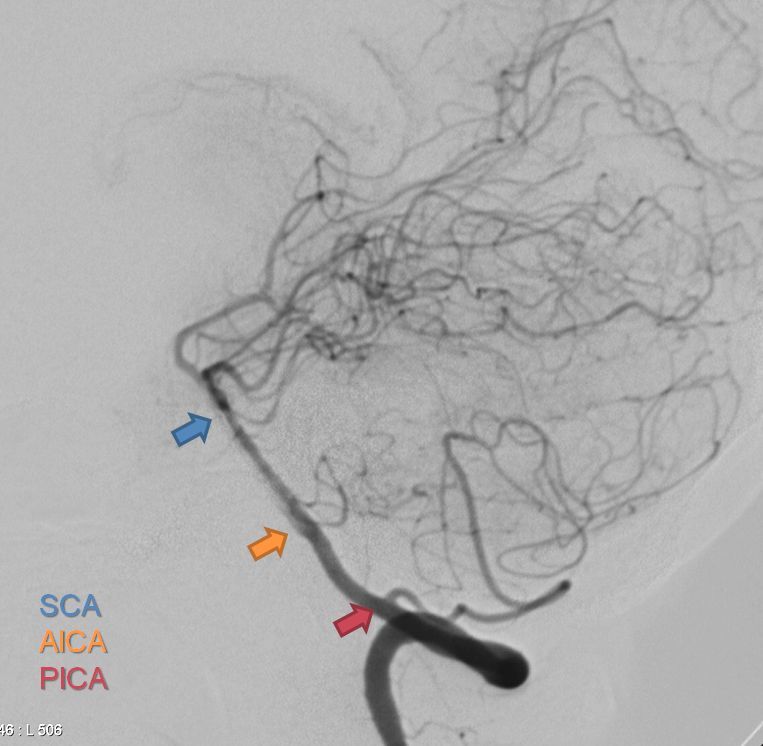

Which artery?

I think AICA (anterior inferior cerebellar A)